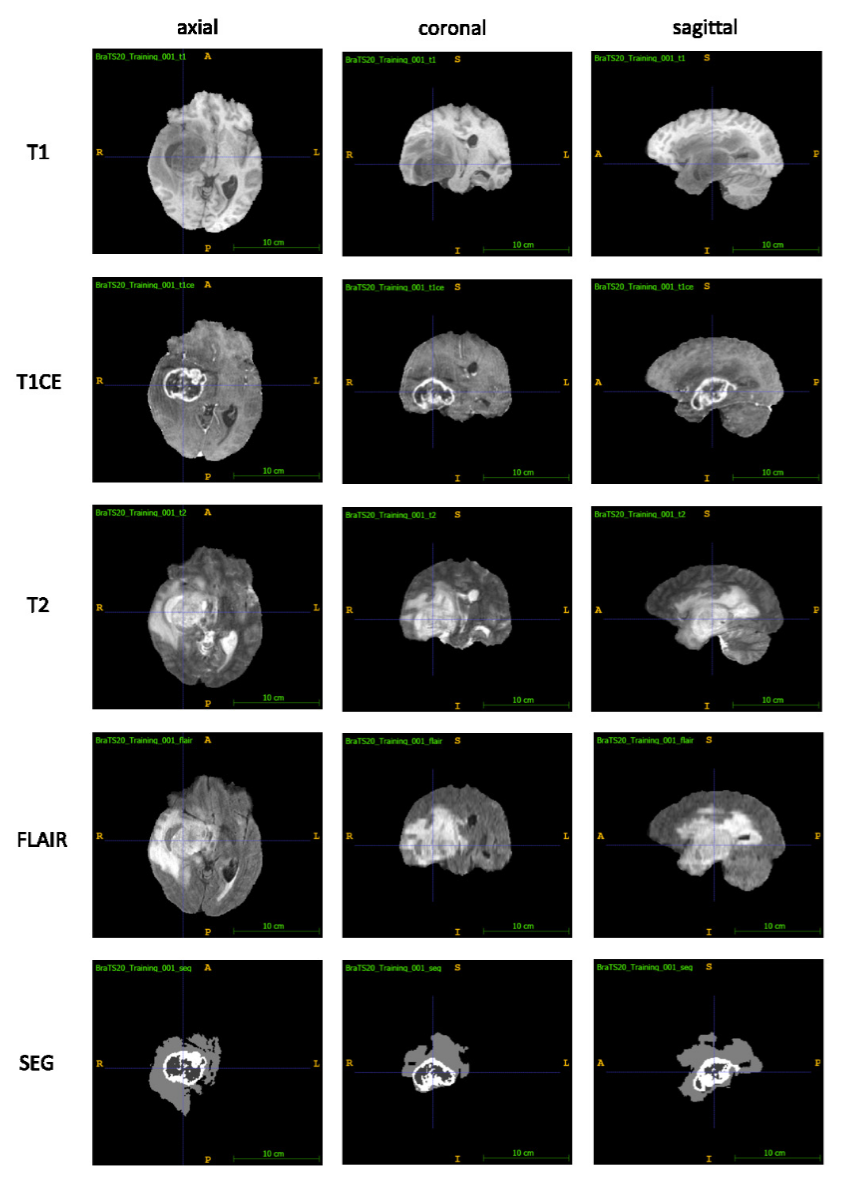

多序列MRI融合策略

多序列信息的价值

不同的MRI序列提供互补的组织信息:

同一脑肿瘤的不同MRI序列对比,显示互补信息

多序列MRI融合效果:展示了T1、T2、FLAIR和DWI四种序列的融合结果。不同序列提供互补的组织信息,融合后的图像包含了更丰富的诊断信息。

算法分析: 多序列融合通过将不同MRI序列的信息整合,提高了诊断的准确性。从运行结果可以看出,四种序列(T1、T2、FLAIR、DWI)被成功融合为一个4通道的图像。每个序列都经过Z-score标准化,确保强度范围的统一。融合后的图像保留了各个序列的互补信息,为深度学习模型提供了更全面的输入特征。